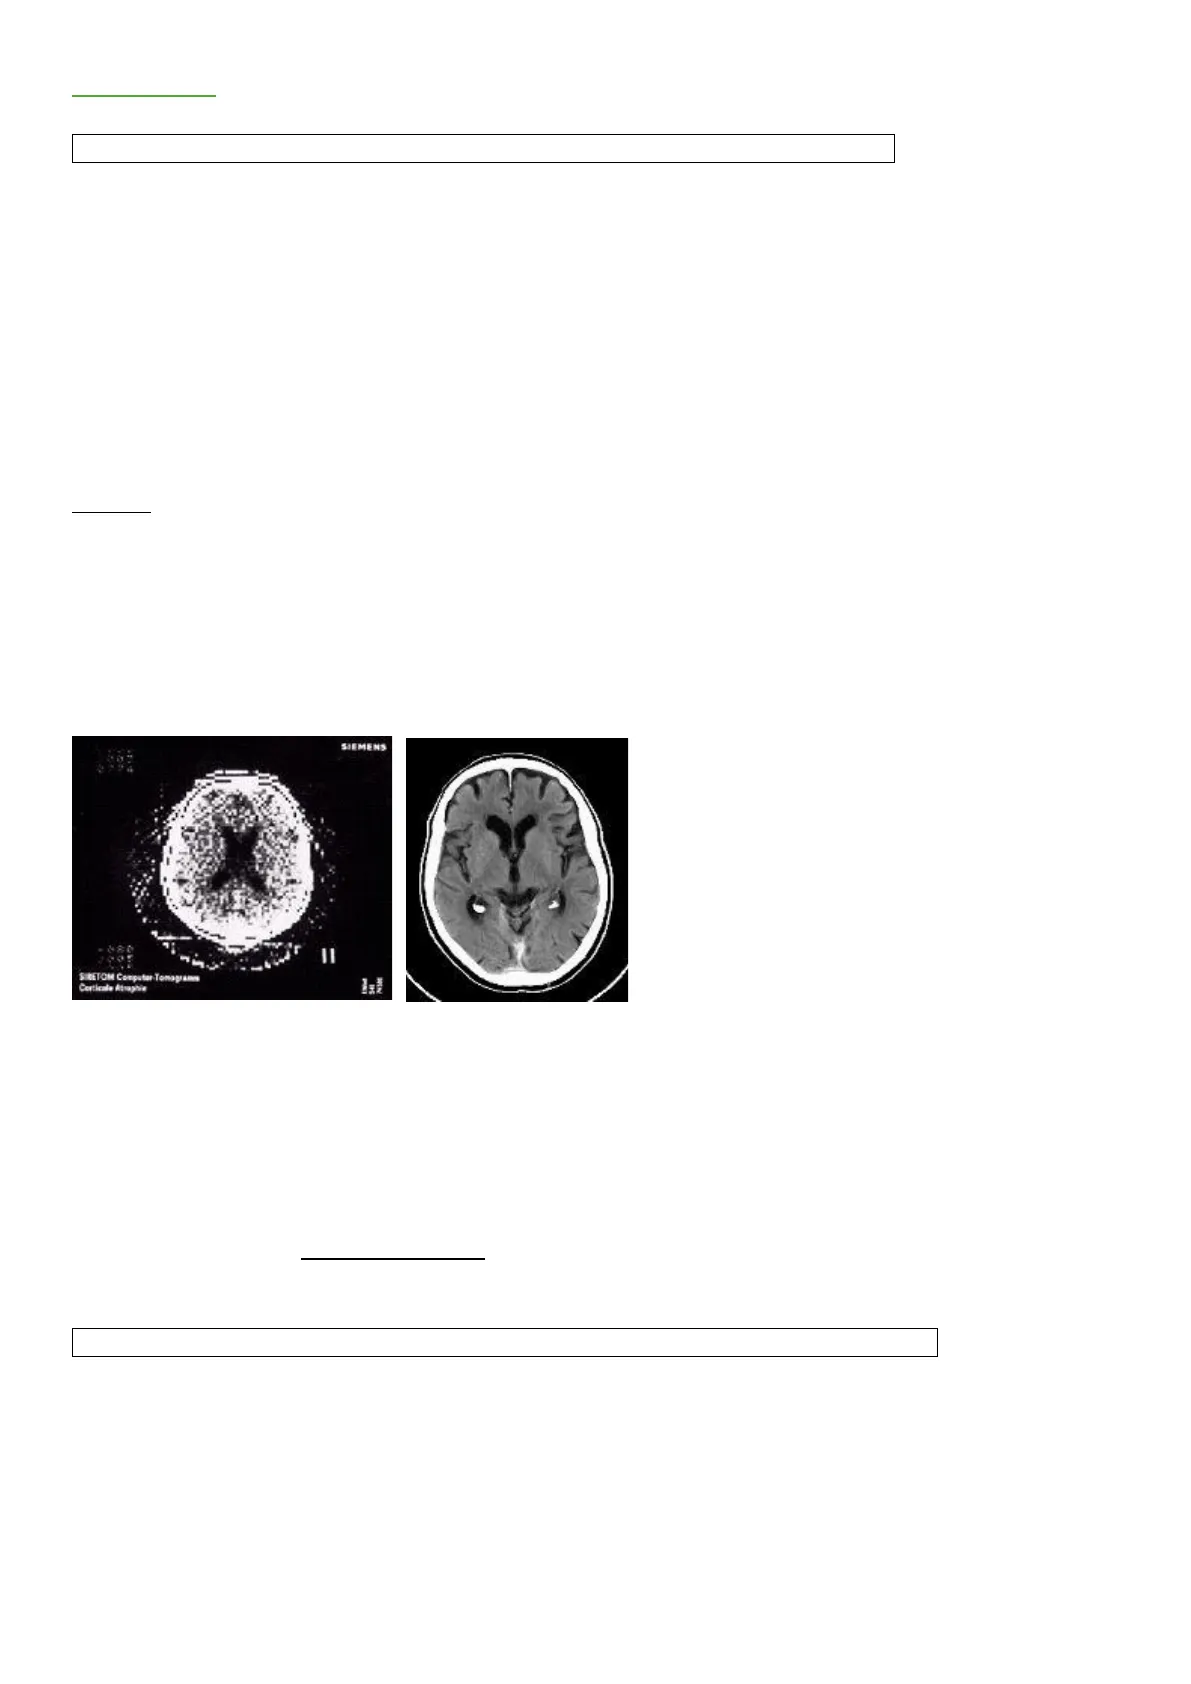

1917 -> signor Radon propone teorema per cui, conosciute tutte le possibili proiezioni, è possibile ricostruire un oggetto 3D 1961 -> Oldenford e Cormack propongono utilizzo elaboratore elettronico per risalire a differenze di densità di oggetti fisici sfruttando energia RX rilevata da detettori a cristalli sensibili 1971 -> Hounsfield realizza il primo prototipo di Tc basandosi su calcoli matriciali (pensato a una matrice), ogni pixel contiene un numero binario e ogni numero binario si assocerà ad un livello di grigio. SIEMENS II SIRETOM Computer Tomogramm Corticale Atraphie Parte densa encefalo: scatola cranica (bianca) Parte molle: ventricoli (pieni di liquido quindi neri) Nella TC un fascio di Rx strettamente collimato (di un certo spessore) attraversa una sezione corporea seguendo una successione di proiezioni e traiettorie diverse Si eseguono tante proiezioni per visualizzare strutture 3d, si colloca il rilevamento di una densità in un Pixel